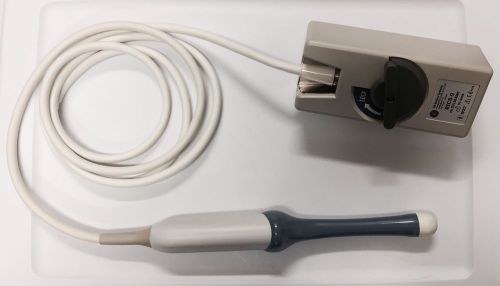

GE RIC5-9 3D/4D Vaginal Ultrasound Transducer Probe

GE RAB4-8-P 3D/4D Convex Abdominal Ultrasound Transducer Probe

GE AB2-5 2D Convex Abdominal Ultrasound Transducer Probe

Siemens / Acuson 9L4 Linear Ultrasound Transducer